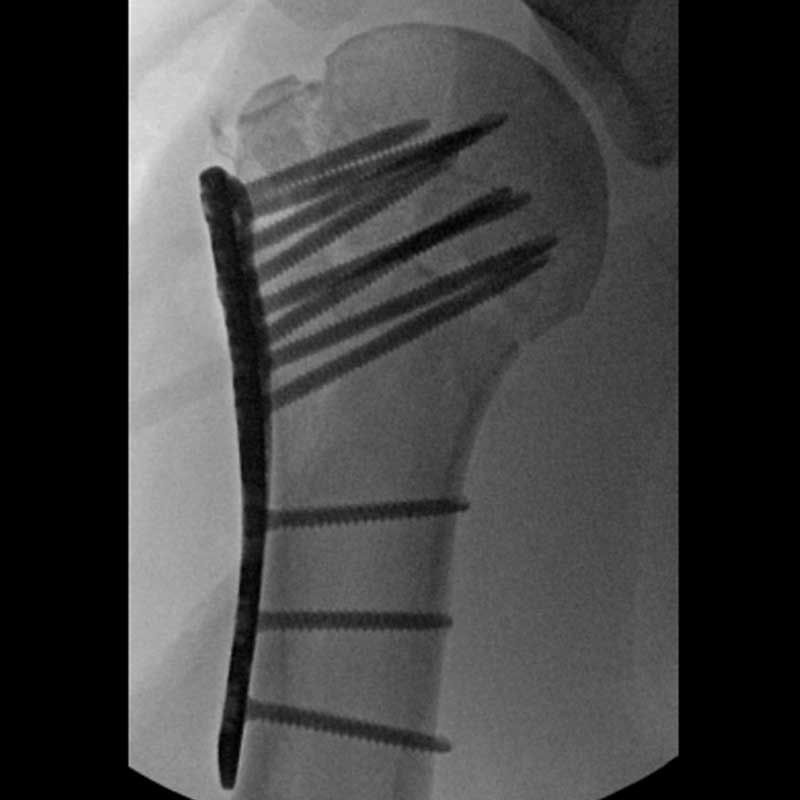

Proximal Humerus Solutions

Plating System

- 40° Polyaxial locking

- Strong & consistent locking at every angle

- Titanium low-profile construct

- Compression before locking

- Locking caps improve fatigue properties and prevent screw back out

- The system allows for precise screw placement independent of the plate position

- Polyaxial drill guides allow for provisional K-wire fixation

- Sutures can be passed before or after osteosynthesis